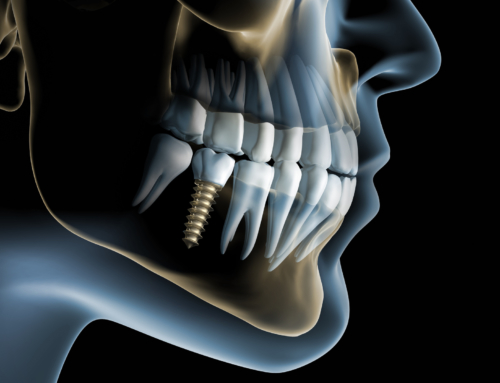

View Larger Image Dental Implantsunrise dentallab2018-09-17T05:56:30+00:00 Project Description Project Details Categories: Implants Share This Post FacebookTwitterLinkedIn Related Projects X-ray Finish